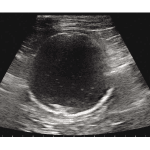

Ultrasound scanning of the appendix

Appendicitis is one of the most common causes of acute abdominal pain in both children and adults, and remains the most frequent abdominal surgical emergency globally, with approximately 50,000 acute appendicectomies performed annually in the UK. Timely diagnosis is key for optimising outcomes with appropriate treatment. Delays in diagnosis and initiation of treatment can lead […]